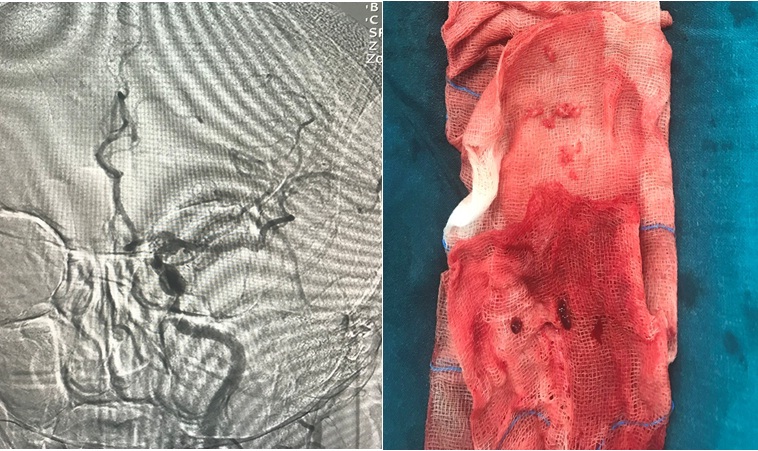

Hình: Các cục huyết khối được lấy ra và hình CLVT sọ não sau 2 ngày.

- Sau can thiệp B/N liệt cải thiện (cơ lực tay chân 3/5)